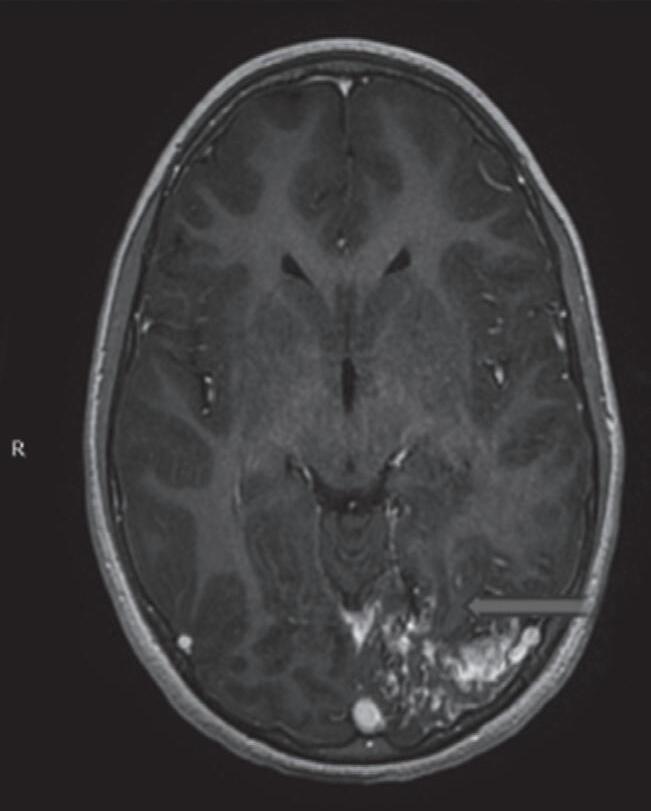

Fig. 1-8. (a-c) RNM T1 com contraste, cortes sagital (a), coronal (b) e axial (c) demonstrando MAV não rota com nidus localizado no lobo occipital à esquerda (setas longas). (d) Arteriografia digital cerebral com injeção de contraste via carótida direita (AP) mostrando a contribuição da carótida direita na irrigação da MAV contralateral. (e,f) Com injeção de contraste via carótida esquerda, em Perfil e AP respectivamente, observa-se nidus compacto nutrido por ramos da artéria cerebral média à esquerda e a veia de drenagem precoce se dirigindo para o seio sagital superior. Projeções em AP (g) e em perfil (h) demonstrando a contribuição do sistema vertebrobasilar por meio de ramos distais da artéria cerebral posterior à esquerda e drenagem para os seios sagital superior e sigmoide à esquerda (setas curtas).

Fig. 1-17. RNM encéfalo T1 com contraste (a) axial e (b) T2 sagital demonstrando MAV grau 5 profunda temporoinsular esquerda com extensão nos núcleos da base. (c,d) Arteriografia cerebral,demonstrando a drenagem venosa profunda para veia cerebral interna (seta azul) com sinais de hipertensão.